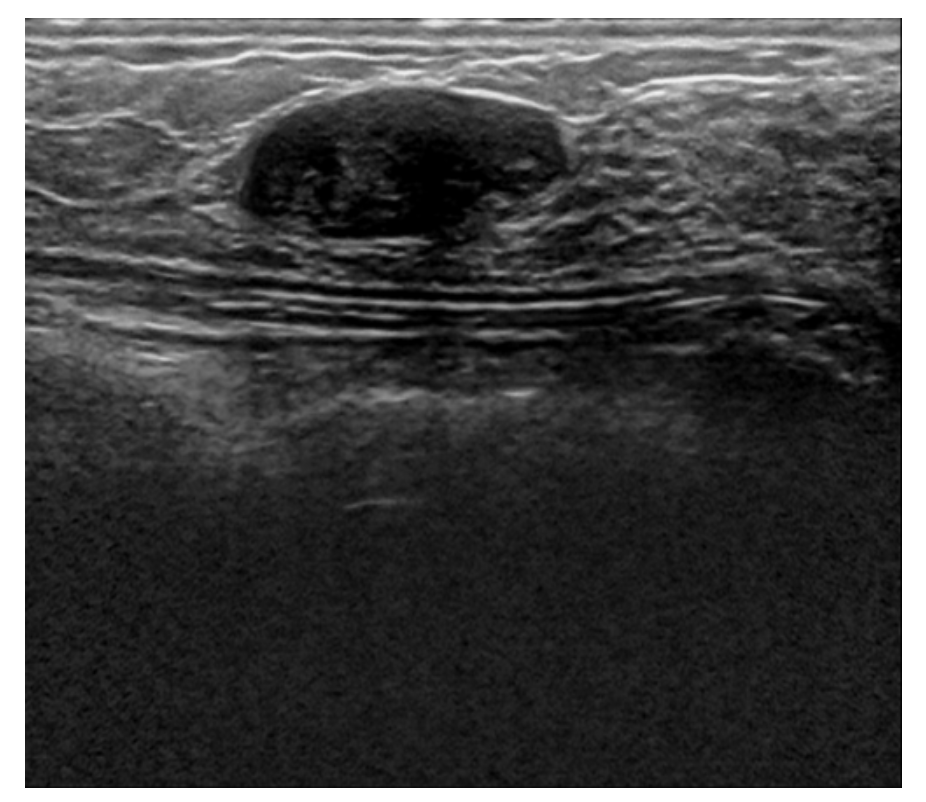

Four datasets were used, the first one is the Baheya dataset which includes a total of 780 ultrasound images. These images are split into three categories Benign, Malignant, and normal, and each category includes 437, 210, and 133 respectively. Also, each ultrasound image has its mask images as shown in the figure below.

The second dataset is Bus-synthetic-dataset, which consists of 500 breast ultrasound images, and each image has its mask same as the first dataset as shown in the figure below.

The third dataset is Thammasat University dataset, which consists of 500 breast ultrasound images, however, every image doesn’t have a mask.

The fourth dataset is Spain Dataset sometimes referred to as Dataset B, which consists of 163 images, however, every image doesn’t have a mask.